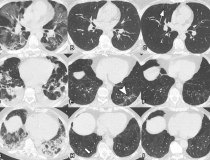

This photo gallery shows the variety of radiological presentations of COVID-19 (SARS-CoV-2) in medical imaging, including computed tomography (CT), radiograph X-rays, ultrasound, echocardiograms and magnetic resonance imaging (MRI). The radiology images show examples of typical COVID pneumonia in the lungs and the numerous complications the virus causes in the body in multiple organs, including the brain, kidneys, heart, abdomen and vascular system.

Ultrasound, especially hand-held ultrasound imaging devices, have become a primary imaging modality for novel coronavirus because of the ease to bag the device and sterilize it after use. CT and mobile X-ray systems are also used as front-line imaging systems for COVID-positive or suspected COVID patients.